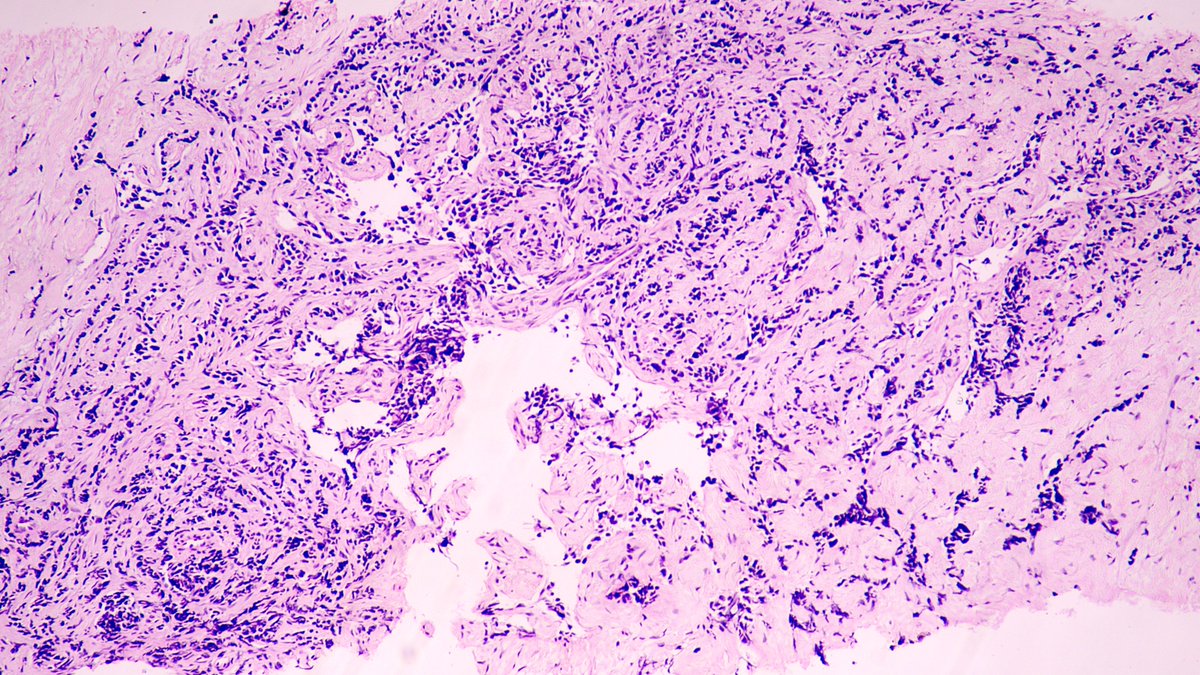

65 year old man posterior auricular neck deep dermal nodule. easy peezy?#dermpath #PathTwitter #dermatology Etan Marks, DO @ArjunRamaiya1 Lorand Kis Olaleke Folaranmi Tristan Rutland MBBS FRCPA IFCAP Trish Stratus Marcelasaeblima. Allison Osmond MD MSc FRCPC Ahmed Alomari, MD Gonzalo De Toro